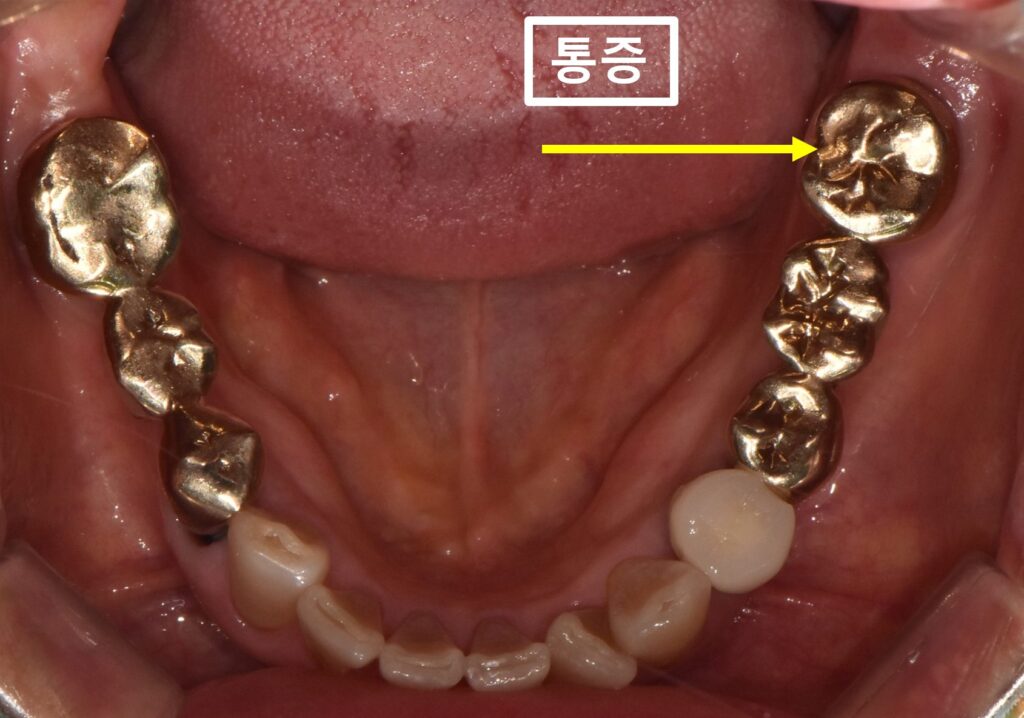

먼저 입안 사진입니다.

노랑색화살표가 가리키는 치아가

계속 불편하고, 주변 잇몸도 양치할때 아파서

집근처 치과에 갔는데

금으로 씌워진 치아는 이상이 없다고

들었다고 하셨습니다.

저도

치아 두드려보거나

찬물 혹은 따뜻한 물에 통증이 있는지,

잇몸 아래로 염증으로 인한 주머니가 있는지

면밀한 검사를 했지만

치아 자체에는 큰 이상이 없었습니다.